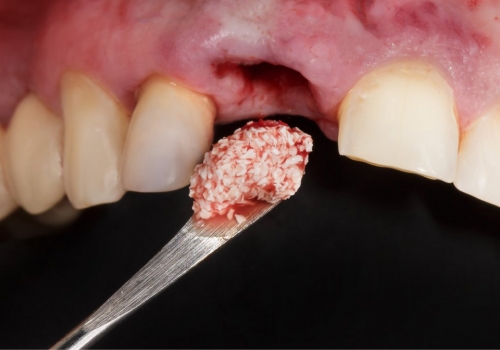

Bərpa texnikasının müəyyən edilməsi, sümüyün hansı bölgədə, hansı miqdarda itirilmiş olmasına bağlı olaraq müəyyənləşdirilir. Bərpa üçün tətbiq edilən sümük materialları pasiyentin öz donor bölgələrindən xüsusi metodlarla qazanılmış sümüklər, o cümlədən digər fərdlərdən alınmış və xüsusi qaydada hazırlanmış materiallar, heyvan mənşəli sümükəvəzləyici materiallar və sintetik materiallar olaraq ayrılır.

Bərpa zamanı yerinə görə bu materiallar ya ayrı-ayrılıqda, ya da kombinə olunmuş şəkildə tətbiq oluna bilir. Gündəlik təcrübədə həmçinin pasiyentdən götürülmüş qan nümunələrindən alınmış yüksək bərpaedici xassəyə malik materiallar (PRF) da uğurla tətbiq olunur. Sümükartırma metodlarının tətbiqi sayəsində, çənədə implantların yerləşdirilməsi üçün yetərsiz sümük həcmi olan bölgələrdə sümük miqdarı yetərli duruma gətirilir, uyğun boy və diametrə uyğun implantlar uğurla tətbiq olunur.